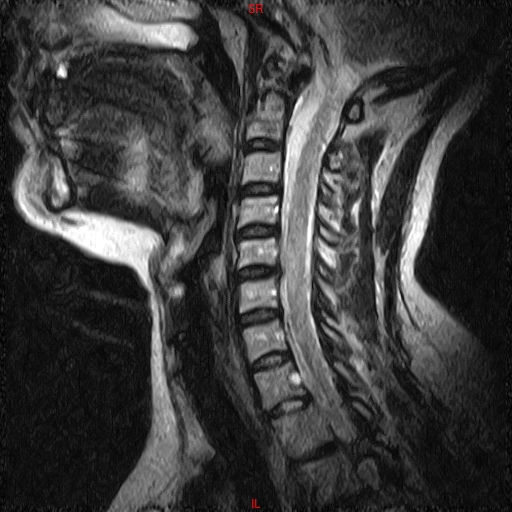

• RESONANCIA PATOLÓGICA DE C.CERVICAL -  SAG T2